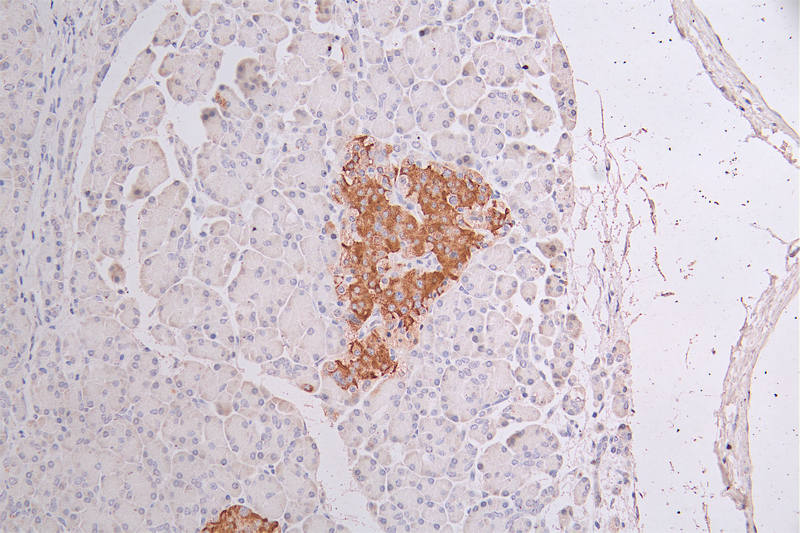

IHC image of CSB-RA582749A0HU diluted at 1:50 and staining in paraffin-embedded human pancreati tissue performed on a Leica BondTM system. After dewaxing and hydration, antigen retrieval was mediated by high pressure in a citrate buffer (pH 6.0). Section was blocked with 10% normal goat serum 30min at RT. Then primary antibody (1% BSA) was incubated at 4°C overnight. The primary is detected by a Goat anti-rabbit polymer IgG labeled by HRP and visualized using 0.34% DAB.